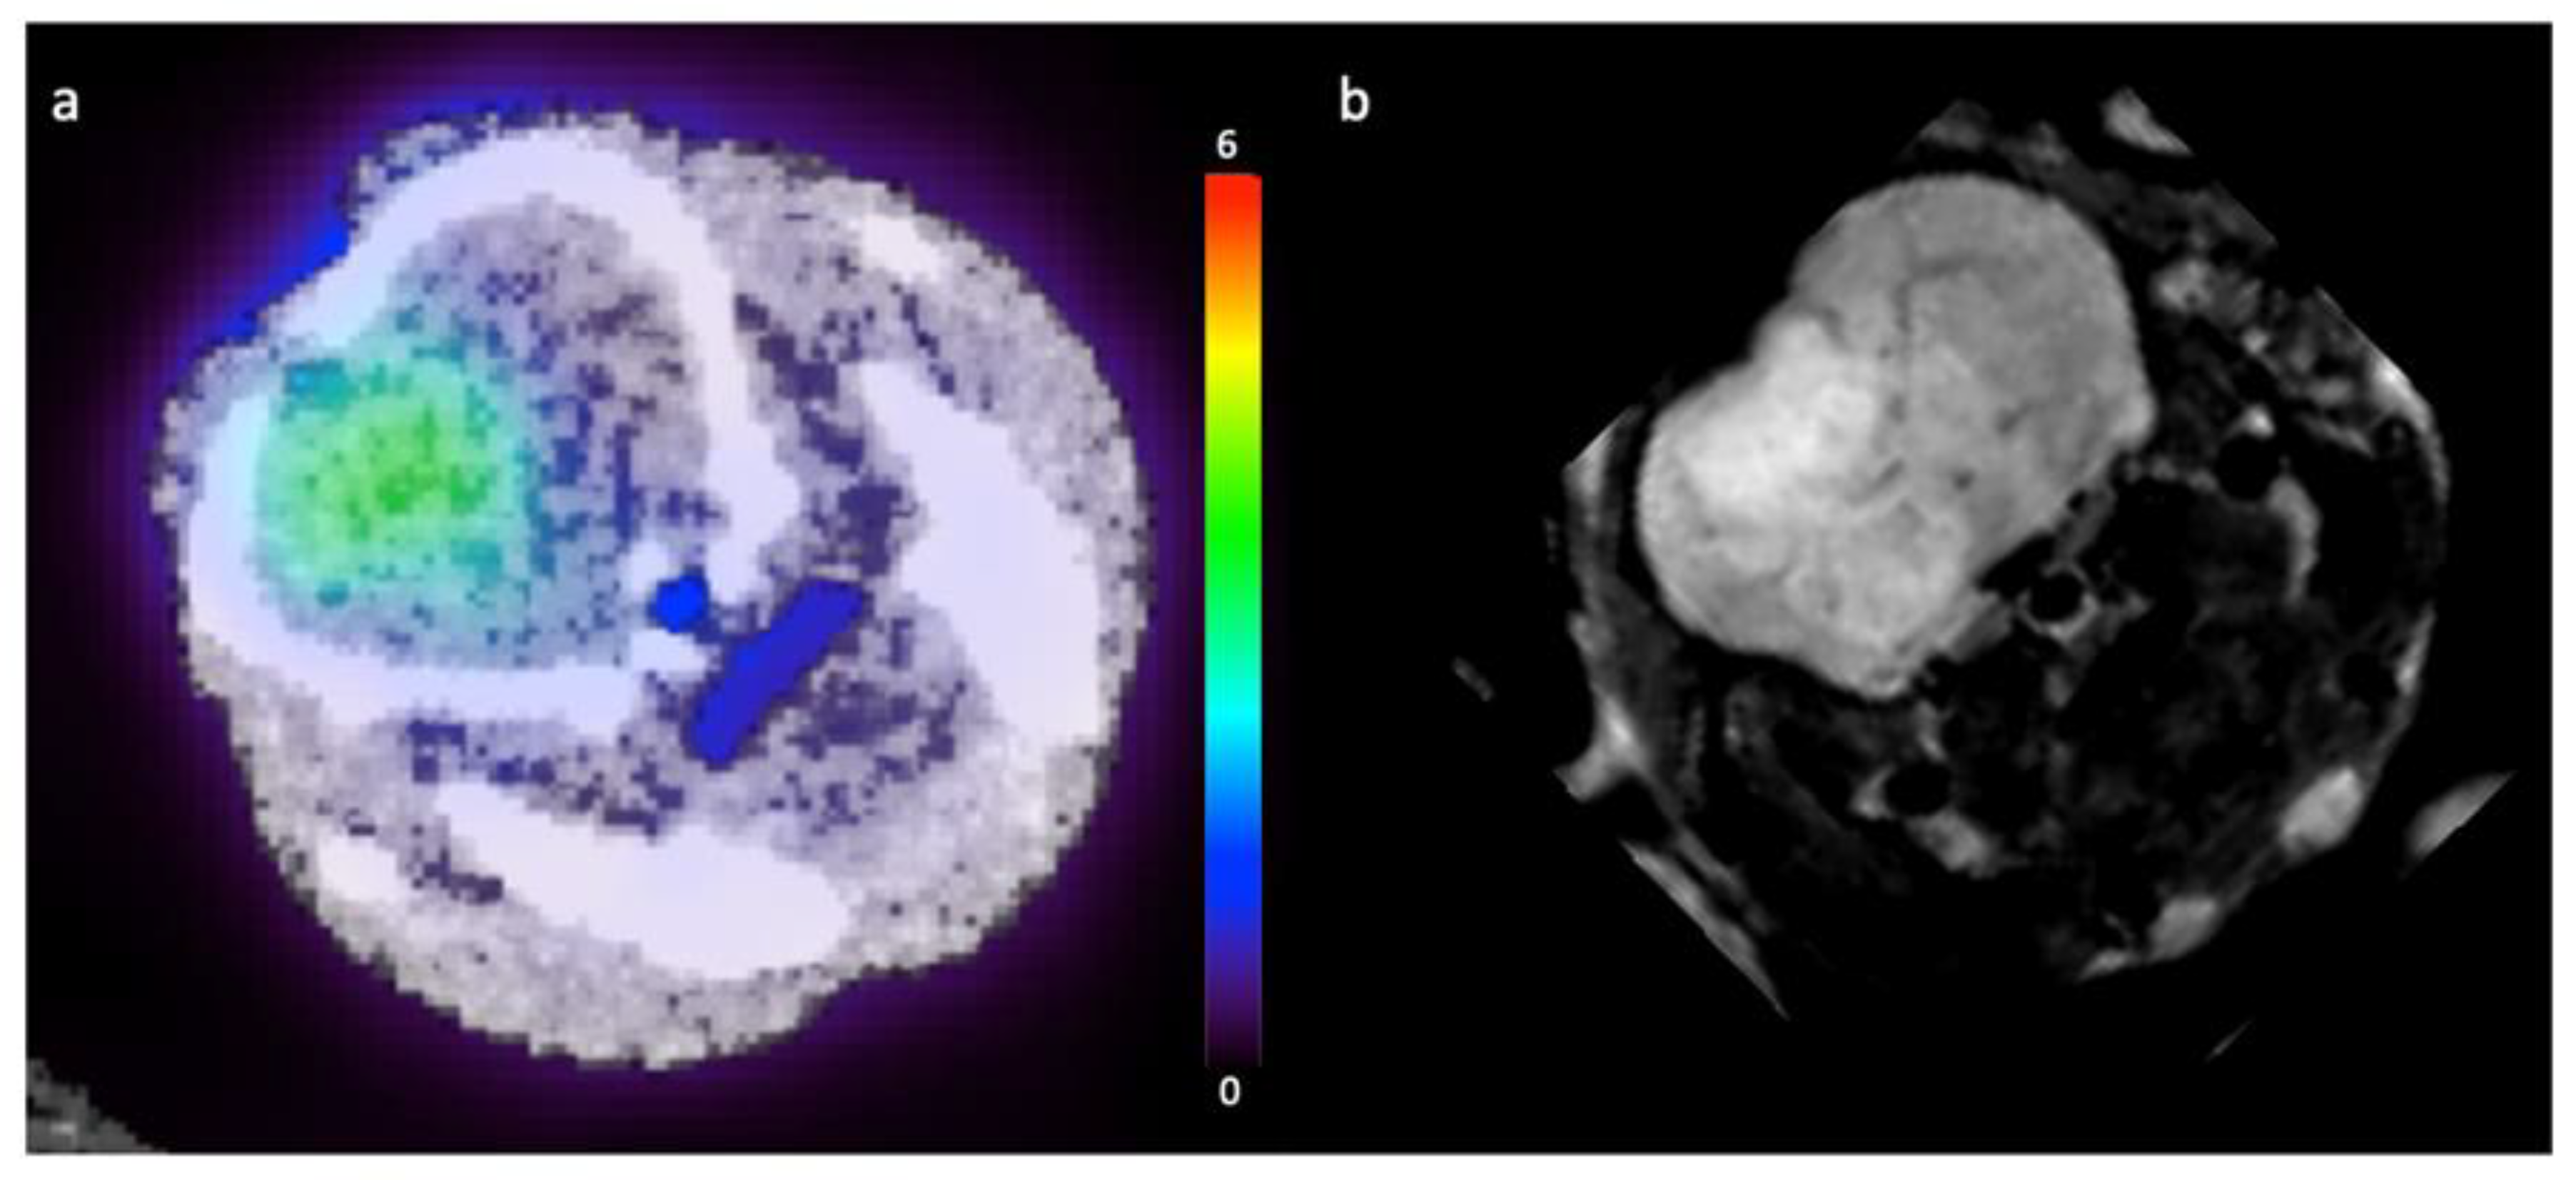

3.3. Pre-Clinical Results

4. Discussion